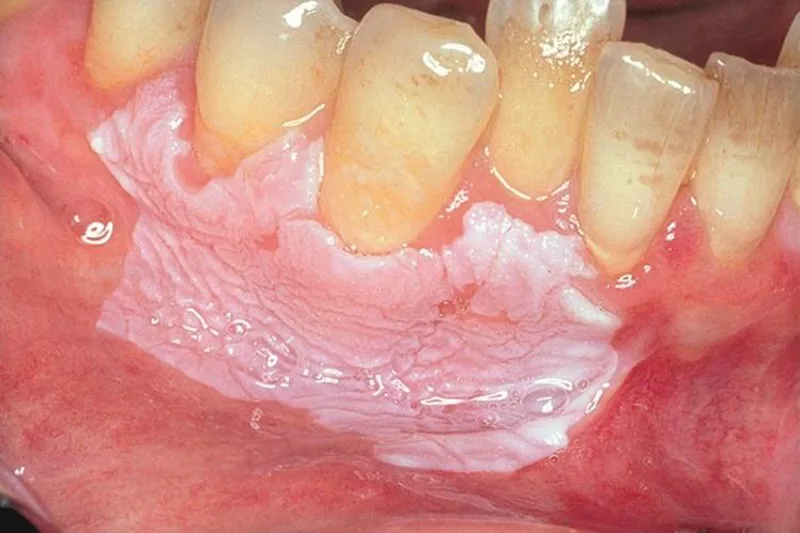

- Morsicatio buccarum: Uregelmæssig, flosset hvidlig forandring i den del af slimhinden, der kan påbides. Årsagen er habituel kindbidning, og forandringen normaliseres ved stop af uvanen.